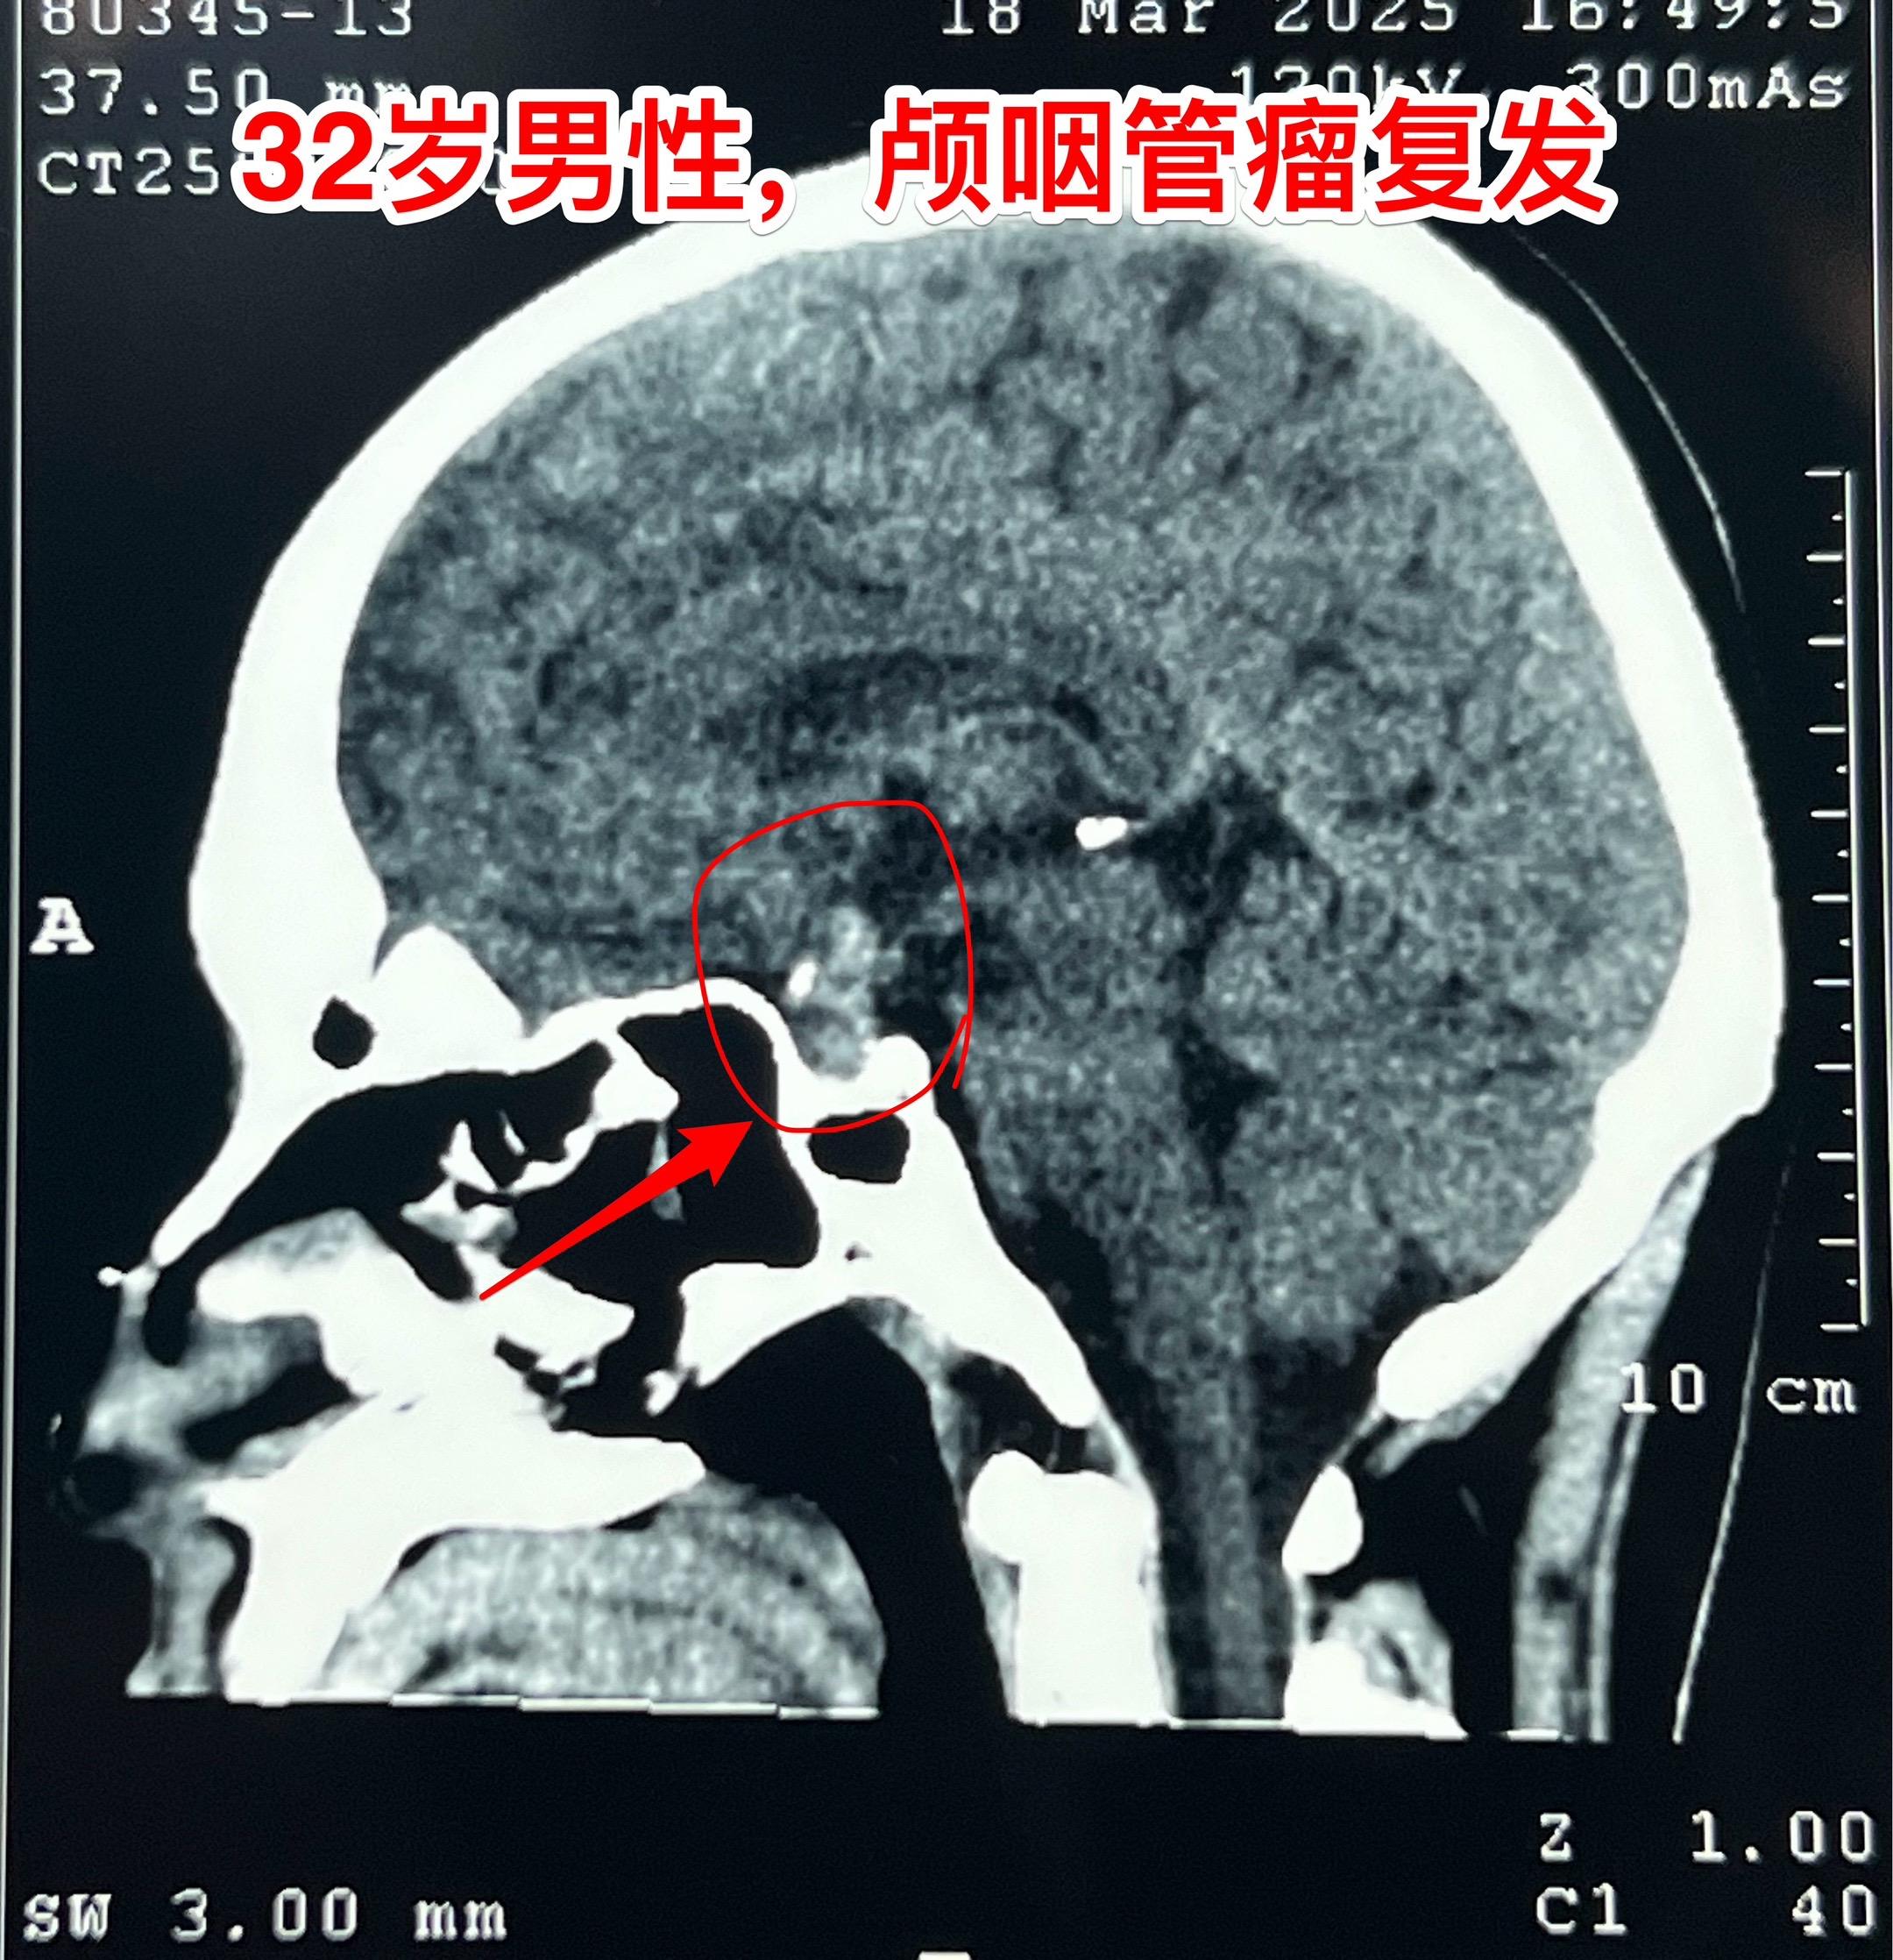

3月28日两个颅咽管瘤手术 两个都是经鼻手术手术后复发的颅咽管瘤手术。我采用了开颅手术。 第一个是64岁山西人,颅咽管瘤手术后再次出现视力下降,复查磁共振显示肿瘤复发。肿瘤是囊性乳头型颅咽管瘤,没有钙化。 第二个是32岁的湖南小伙。肿瘤有钙化。 今年春节后我科颅咽管瘤中经鼻手术后复发的病人比例明显升高了。与近十年经鼻内镜手术广泛开展是有关系。 无论是哪种手术方案,只有效果好、复发率低,病人才会满意。